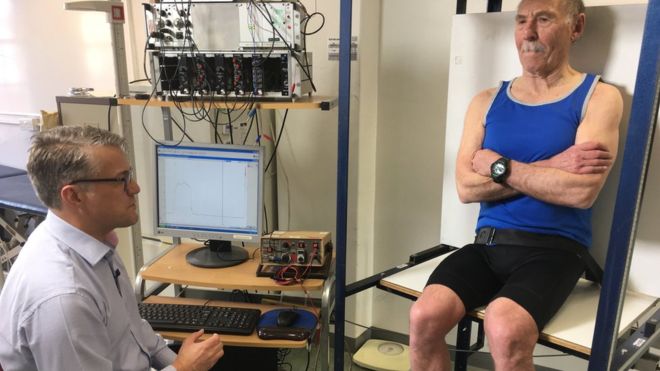

Over 80 but as healthy as a 20-year-old: How exercise in old age prevents the immune system from declining http://bbc.in/2FqAWvy

pic.twitter.com/1gPdBuhu4W